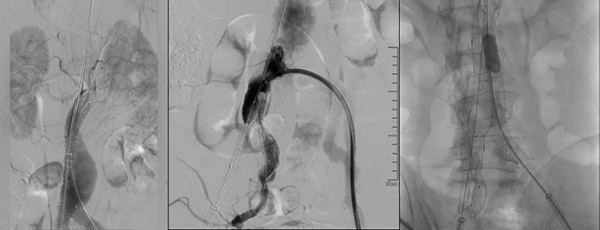

手术当天,肿瘤介入团队为患者实施腹主动脉-双侧髂动脉覆膜支架置入术。术中精准地将支架分别置入腹主动脉和左侧髂总动脉、右侧髂总及髂内动脉。成功将动脉瘤与血管腔分离,达到腔内隔绝的同时,也避免了分支血管缺血。实现了所有分支动脉完整保留,无任何并发症的目标。历时3.0个小时,微创手术取得成功,DSA显示动脉假腔完全消失,血管恢复正常形态,达到预期目的。术后患者各项指标均恢复良好,并已康复出院。 术前造影以及确定肾动脉、主要血管位置 主动脉支架手术:血管内的神奇“修补匠” 主动脉支架释放 髂内动脉支架释放 球囊扩张确保支架完全释放 手术前后对比———术后DSA显示假腔消失,腹主动脉血管恢复正常形态 此次手术的成功开展,为沈阳十院在大血管疾病介入治疗方面的进一步发展奠定了基础,也为未来类似病例的治疗提供了宝贵的经验。沈阳市第十人民医院肿瘤介入科开展了多种疾病的介入治疗。在血管疾病方面再上新高,开展主动脉夹层、主动脉瘤、下肢动脉硬化、下肢深静脉血栓等疾病的介入治疗。在实体肿瘤方面突破进取,开展肺、肝脏、胰腺、胆囊等恶性肿瘤微创介入诊疗技术。在危重症领域上持之以恒,开展咯血、肺栓塞、消化道呕血等疾病的介入治疗。未来,肿瘤介入科团队,将继续致力于技术的创新与推广,为更多患者带来生命的福音和健康的保障。